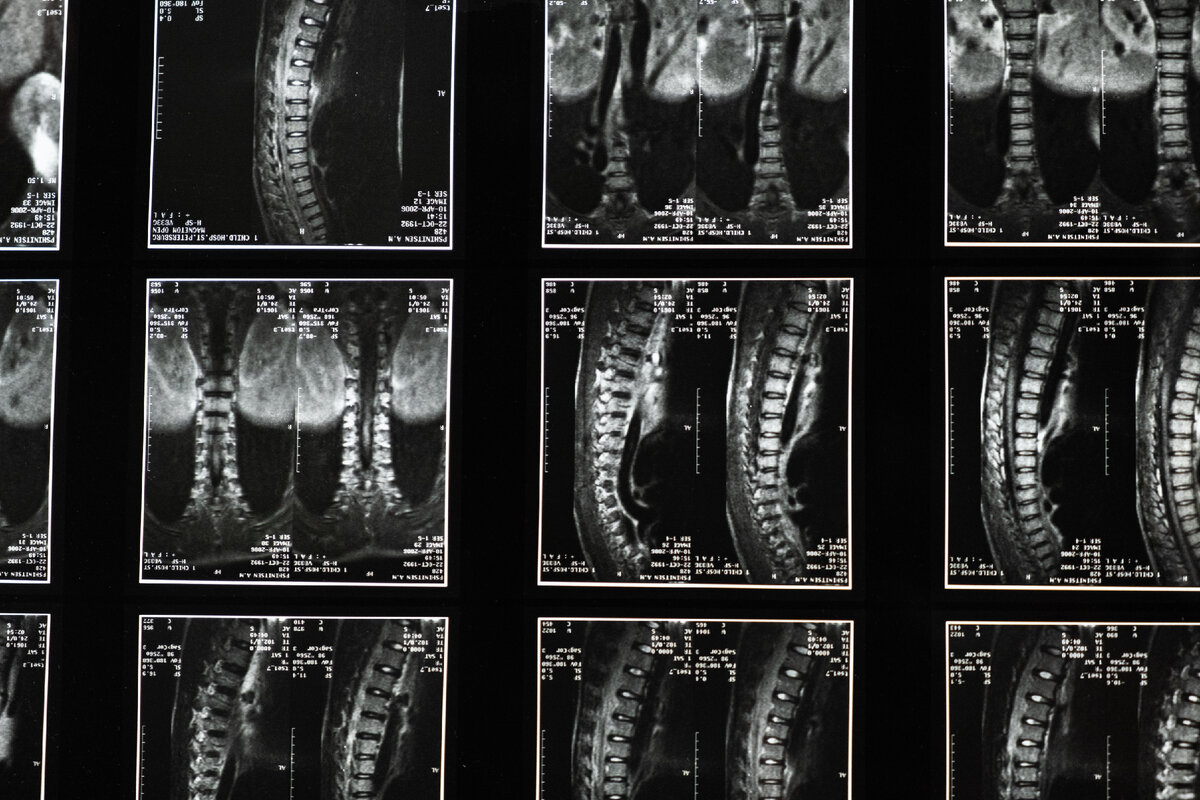

Искривление позвоночника – распространенная патология, которая встречается как у детей, так и у взрослых. Со временем такая проблема склонна прогрессировать, что приводит к появлению сколиоза. Это заболевание характеризуется искривлением всего позвоночного столба, провоцирует серьезные боли в спине и даже способно повлиять на работу внутренних органов. В запущенных случаях болезнь лечится хирургическим способом. На более ранних стадиях используются консервативные методики, одной из которых является массаж. Насколько такая процедура эффективна? Давайте разбираться. Почему возникает искривление позвоночника? Сколиоз представляет собой деформацию позвоночного столба в трех плоскостях, по типу буквы S или C. Появляется такая патология на фоне различных факторов: Малоподвижный образ жизни и сутулость, вопреки распространенному мнению, на развитие патологии практически не влияют. В большинстве случаев сколиоз появляется в период интенсивного роста позвоночника и имеет неустановленные причины

Искривление позвоночника – распространенная патология, которая встречается как у детей, так и у взрослых. Со временем такая проблема склонна прогрессировать, что приводит к появлению сколиоза. Это заболевание характеризуется искривлением всего позвоночного столба, провоцирует серьезные боли в спине и даже способно повлиять на работу внутренних органов.

Сколиоз представляет собой деформацию позвоночного столба в трех плоскостях, по типу буквы S или C. Появляется такая патология на фоне различных факторов: